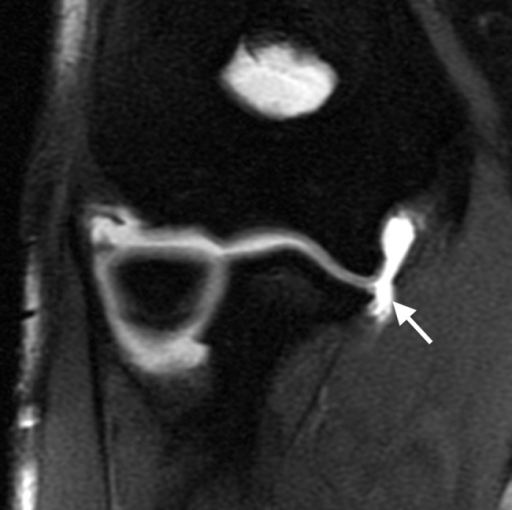

An injury to the ucl may take the form of either an incomplete tear (a grade. Wint on torn ulnar collateral ligament elbow: Injury to these medial stabilizing structures is typically caused by chronic microtrauma from repetitive valgus stress during the acceleration phase of throwing. Incomplete tear of a ligament with moderate functional impairment moderate pain and swelling mild to moderate bruising tenderness over involved structures some loss of motion and function mild to moderate instability. Treatment involves anatomic repair or reconstruction which reliably. Ulnar collateral ligament injury of the elbow is a sprain (tear) of one of the ligaments on the inner side of the elbow. The ulnar collateral ligament (ucl) can become stretched, frayed or torn through the stress of repetitive throwing motions, causing ulnar collateral ligament injuries. Ulnar collateral ligament injury commonly occurs in throwing athletes and may accompany an injury to the overlying common flexor tendon. (severe sprain or partial tear) high signal is seen medial to the ligament, with high signal or partial disruption of the ligament. (minor sprain) high signal is grade 2: Ulnar collateral ligament sprains are serious elbow injuries and must be treated correctly in order to be able to return to your sports activities. Professional pitchers have been the athletes treated most often for this problem. Lateral ulnar collateral ligament tear with posterolateral rotatory instability of the elbow.

The ulnar collateral ligament of the elbow is most often injured by repeated stress from overhead movement. This injury represents an incomplete (grade ii) or a complete (grade iii) rupture of the collagen fibers which connect the ends of the femur (thigh bone) and although uncommon, associated injury to the knee cartilages (medial meniscus or lateral meniscus) or to the acl (anterior cruciate ligament) may. Gery to repair the ligament. The lateral ulnar collateral ligament is the most important in terms of stability. Thumb collateral ligament ruptures, most commonly ulnar collateral (ucl), are athletic injuries that lead to a decrease in effective thumb pinch and grasp. Repetitive throwing motions or overload or stress on a valgus from repetitive pitching or throwing? I or ii sprain), or a complete rupture (grade iii sprain). Garde ii lateral collateral ligament sprain. Lateral ankle injury assessment online course: A lateral collateral ligament (lcl) sprain occurs when there is a tear in the ligaments on the outside of the knee. Wint on torn ulnar collateral ligament elbow: (severe sprain or partial tear) high signal is seen medial to the ligament, with high signal or partial disruption of the ligament. Conventional mri and mr arthrography are the imaging modalities of choice ligament injuries can be classified into three grades.